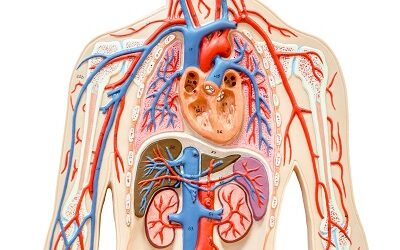

$400.00Cardiorespiratory Performance (Human Biology III)

EXPAND YOUR KNOWLEDGE OF CARDIORESPIRATION Improve your knowledge of the heart, lungs, and blood Improve your personal self-care or assist […]